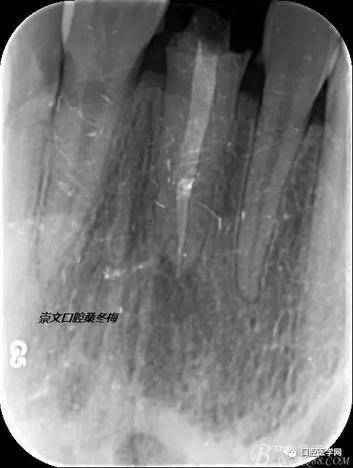

輔助檢查:X線見根尖區(qū)輕低密度影像,根尖1/3見根充物密實(shí)恰填,根管上2/3見折斷纖維樁,與根管密實(shí)。

術(shù)前X線片